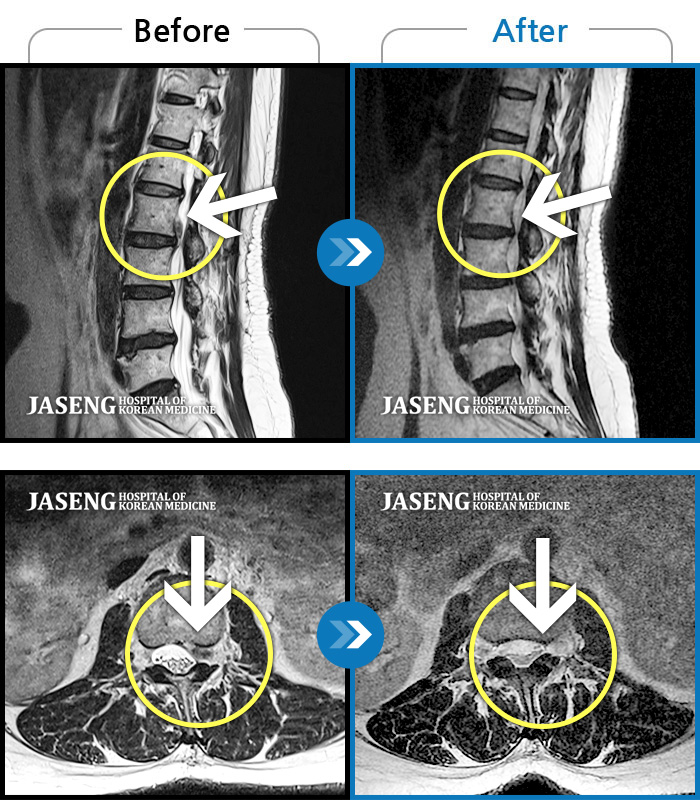

일산 · 배영현 원장

처음 내원 시 허리, 엉덩이가 많이 아프고, 좌측 다리에 힘이 빠지며 감각이 둔하여 정상적인 보행이 힘든 상태셨습니다.

촬영시기

2022.05.24 ~ 2023.05.13

2023.06.01